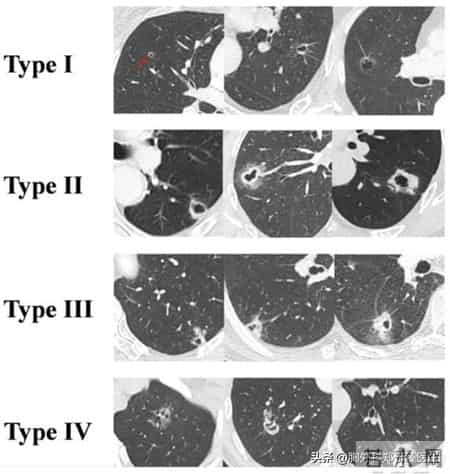

上图是目前认可度比较高的关于囊腔型肺癌影像表现的分类图。

我们可以将其分为四大类:Ⅰ类是薄壁囊腔,囊腔壁的厚度不足两毫米;

Ⅱ类是厚壁囊腔,但是它的厚壁是一个均匀增厚的状态;

Ⅲ类囊腔是疣状囊腔,是在囊腔壁上外伸或内伸,形成有一个疣状赘生物;

Ⅳ类是混合型囊腔,是组织在囊腔内混杂生长,形成了类似散在分布的影像特点。

综合现有的数据,我们可以认为Ⅰ类囊腔是最安全的,基本不会复发。最危险的是Ⅱ类和Ⅲ类囊腔,其相对复发风险较大。